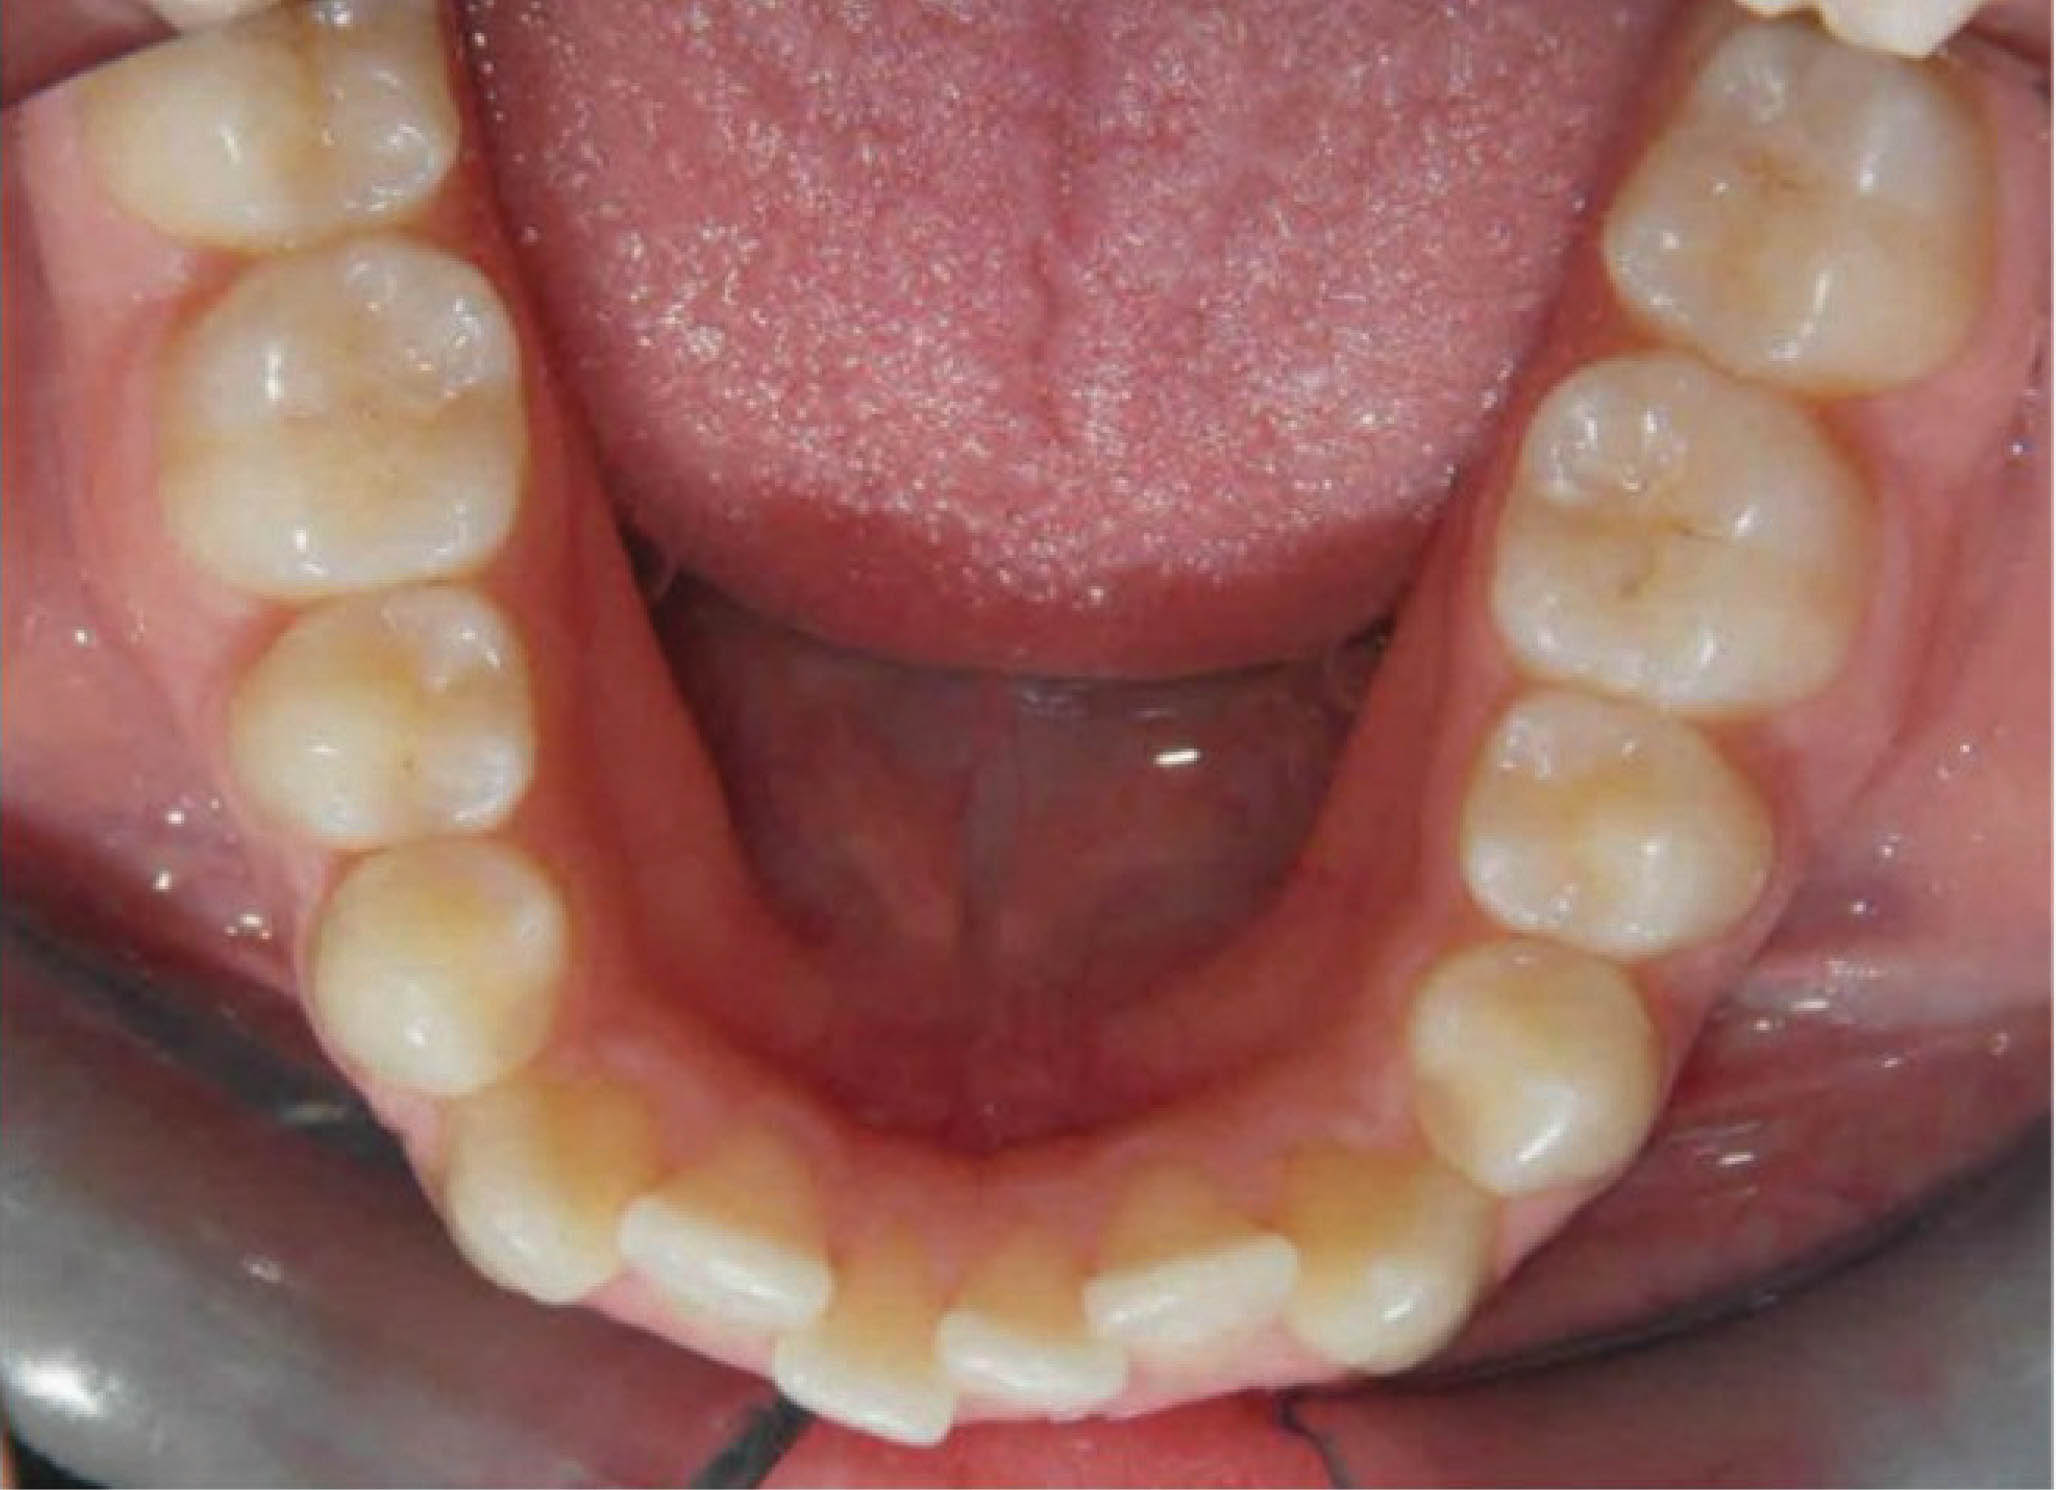

یکی از خوبیهای طراحی کامپیوتری این است که دکتر میتواند میزانهای متفاوتی از اکسپنشن، پروترود نمودن انسیزورها یا استریپ را قبل از شروع کار مشاهده نماید. با این نوآوری میتوانید نتیجه کار و مسیر حرکت دندانها از ابتدا تا انتهای درمان را کنترل نمایید. عرض بین کانینی در مندیبل را هم ثابت نگه داشتیم تا حداکثر ثبات درمان را داشته باشیم. به همین دلیل از ترکیبی از اکسپنشن، پروتروژن انسیزورها و استریپ استفاده نمودیم. اگر به شکل 18-6 که قبل از درمان قوس پایین است نگاه نمایید، سانترال پایین که خیلی لبیالیتر از جایگاه اصلی خود میباشد را میبینید. بنابراین این دندان باید حرکت لینگوالی کند.

شکل 18-6

نتایج درمان (شکل 20-6) و عکس طراحی کامپیوتری (شکل 21-6) خیلی به هم شبیه شدند. عکس OPG هم طبیعی است.